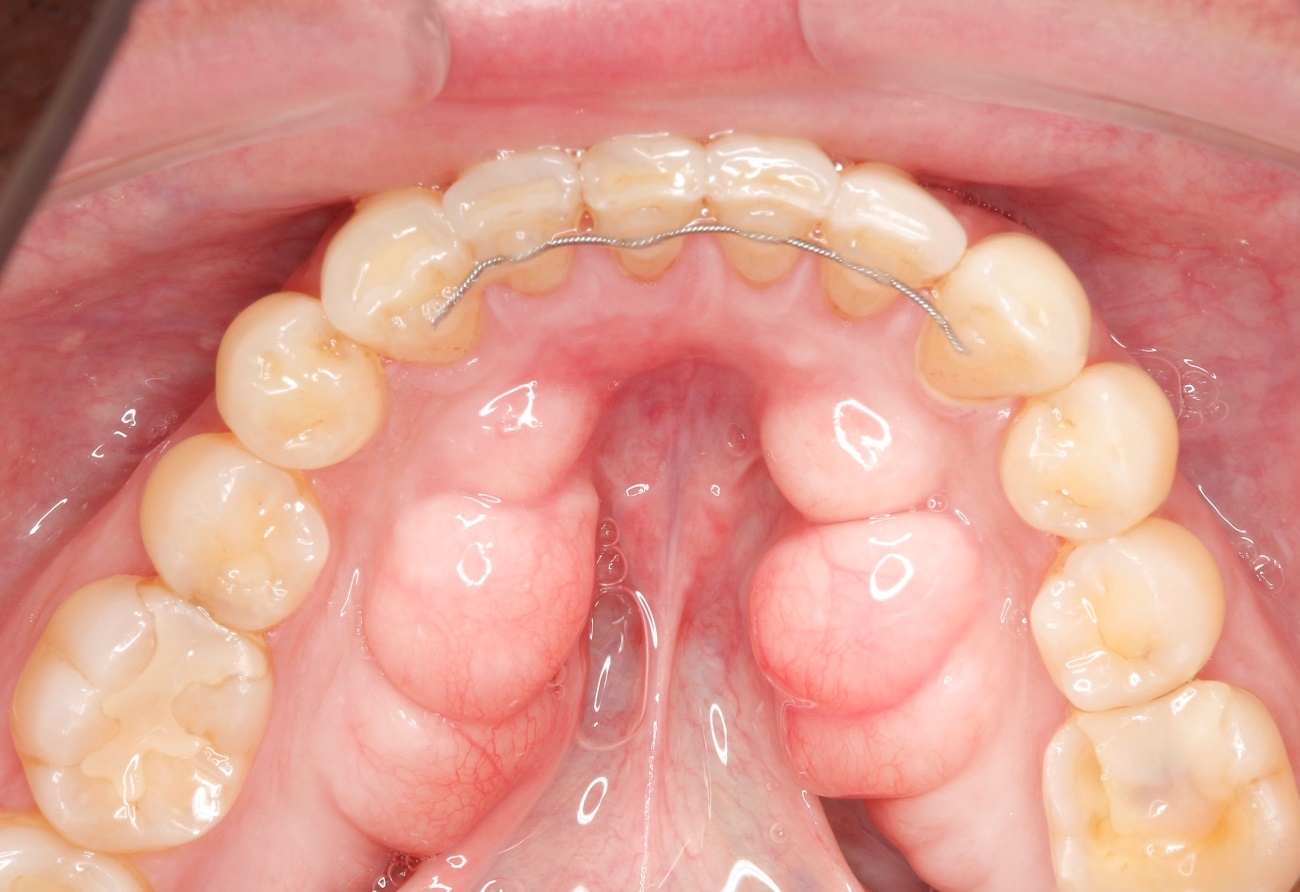

骨隆起(こつりゅうき)とは、口の中にできるコブのようなもので、部分的に骨が異常に発達・隆起し、表面が盛り上がった状態を指します。

骨隆起は、病的な突起物ではなく、通常は身体に悪いものではありません。

遺伝的な要因や食いしばりや歯ぎしりがで力をかけ続けることで、骨隆起ができると言われています。